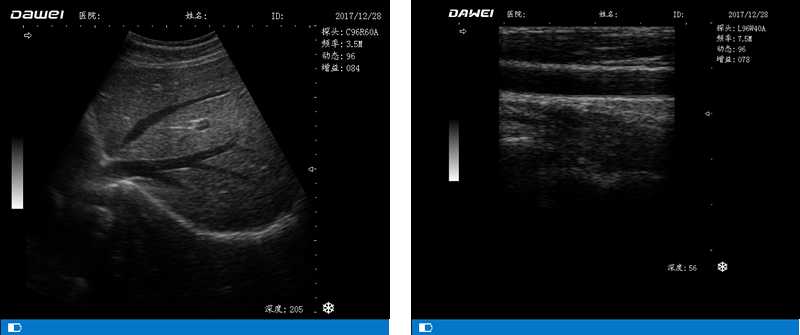

DW-500

筆記本全數(shù)字超聲診斷儀

高陣元 高清晰度 多功能

多倍率顯示 病變診斷更準確